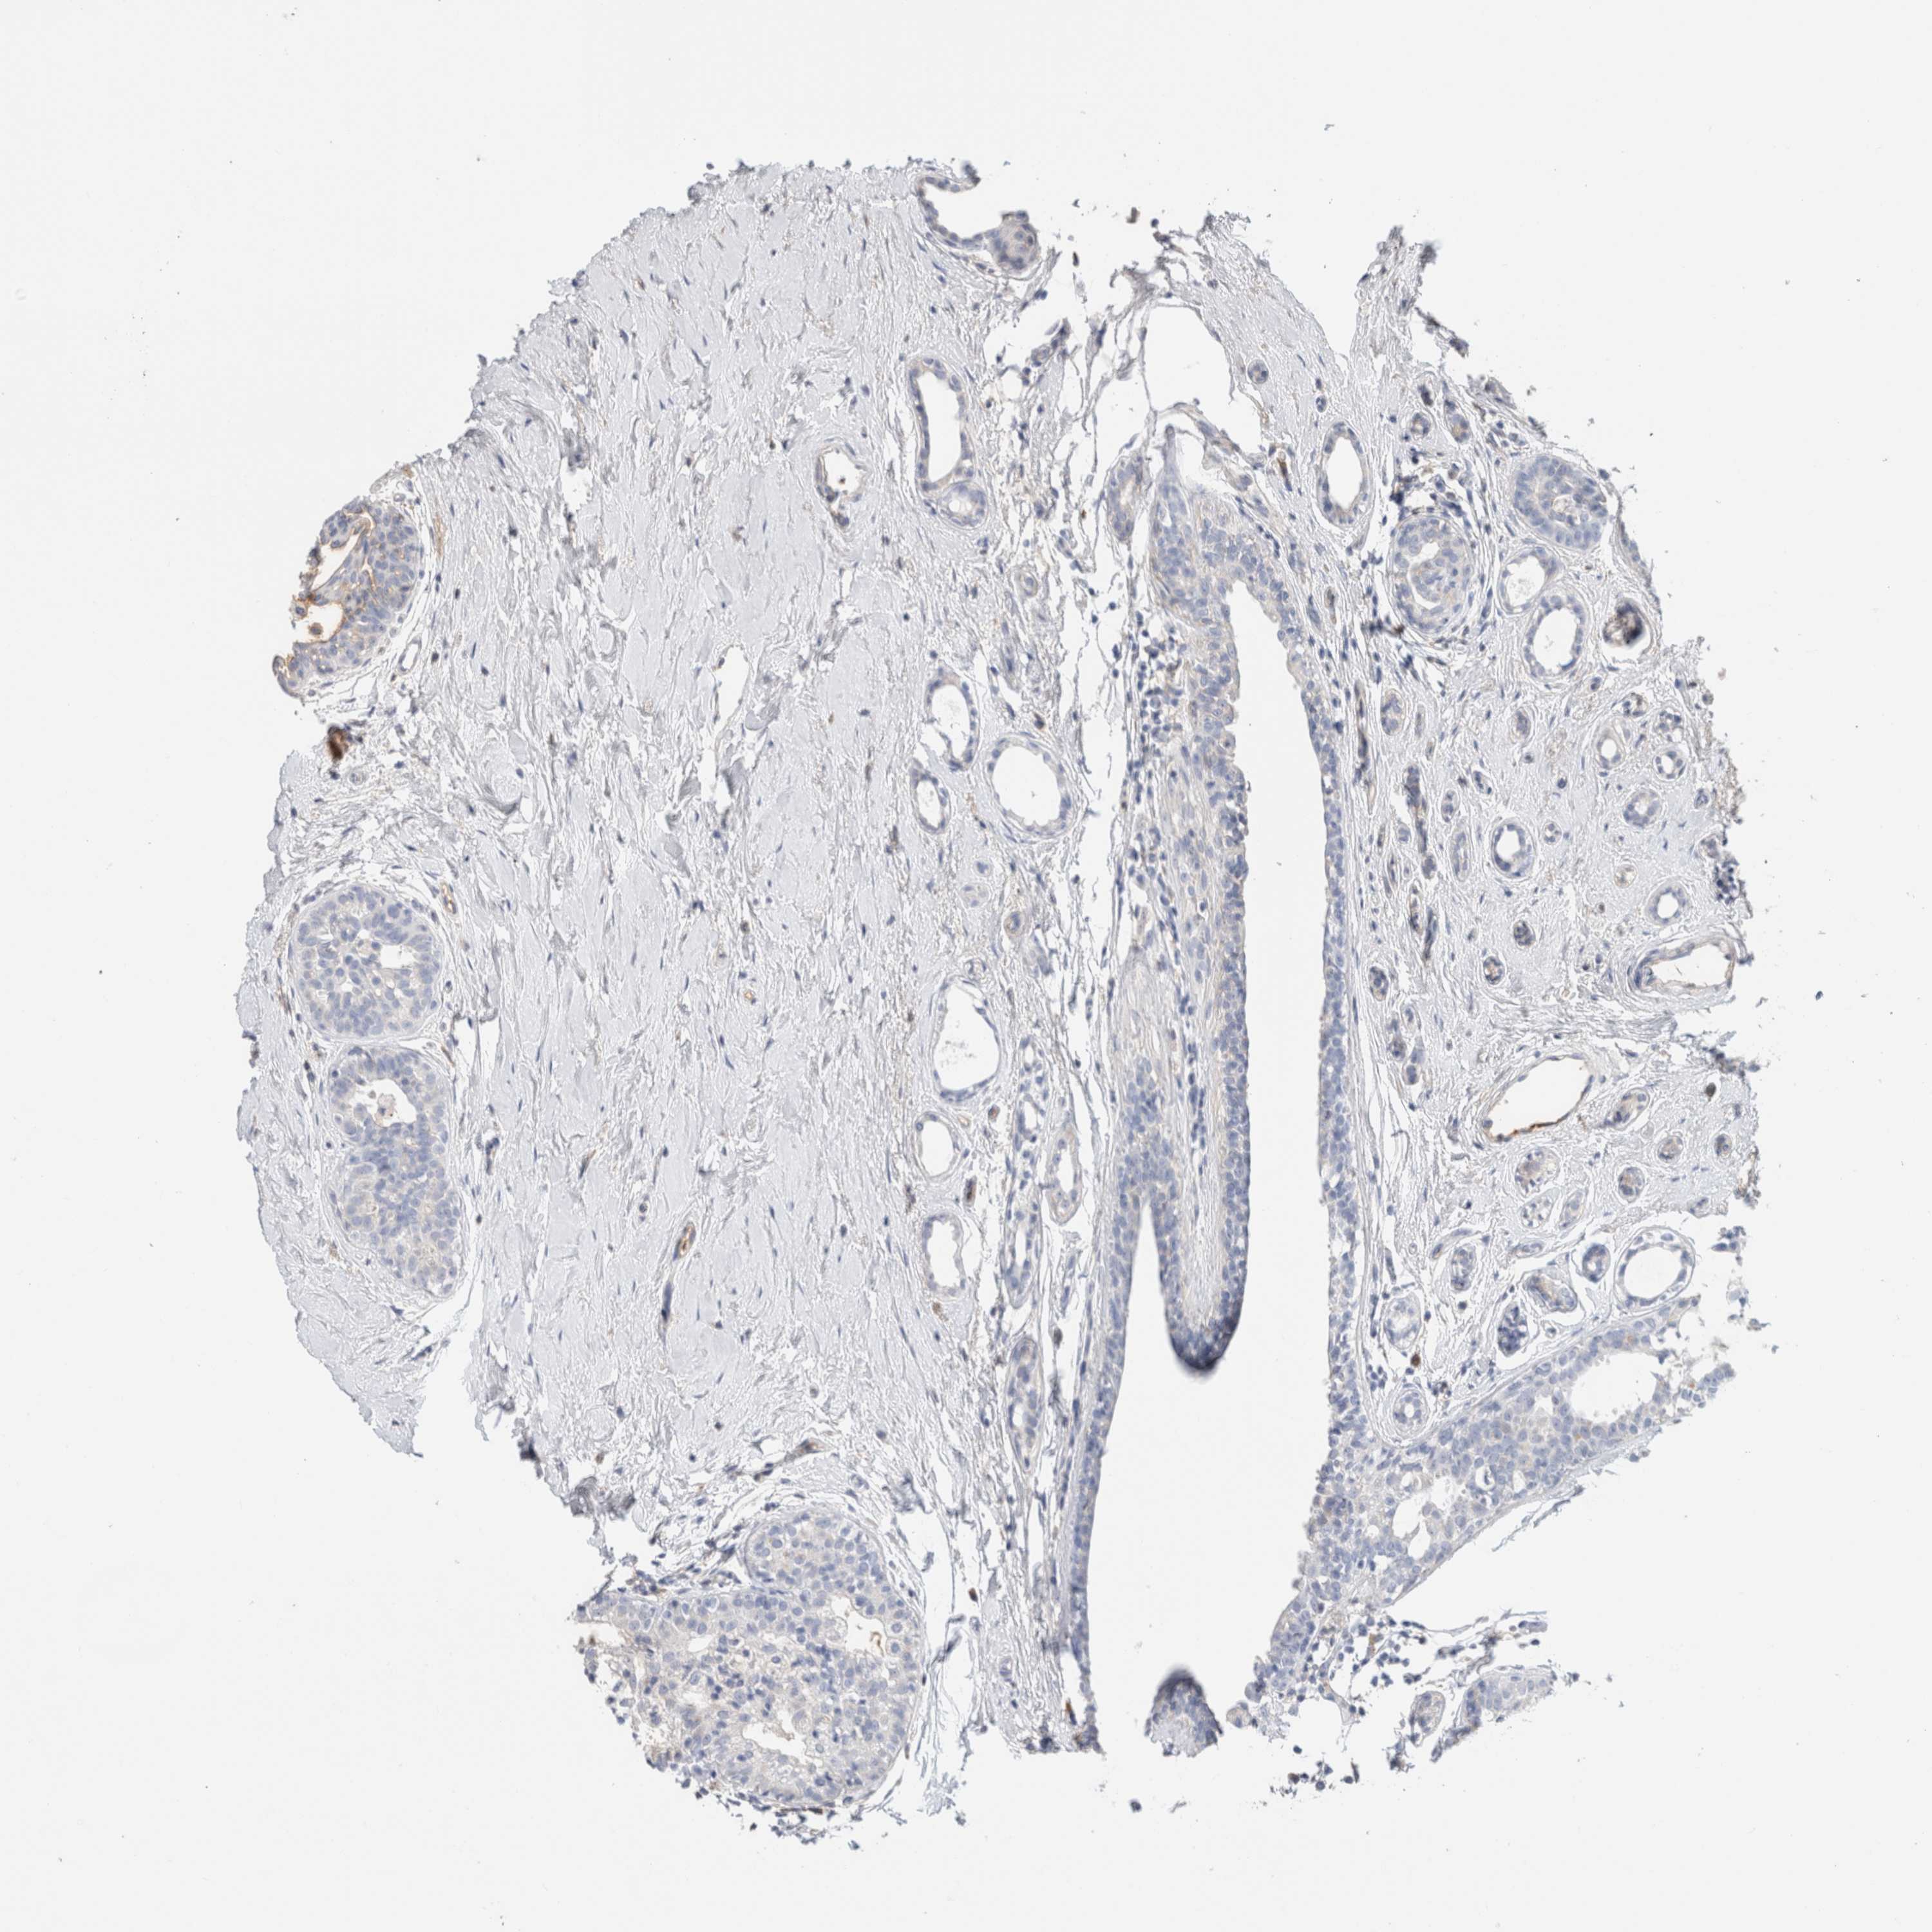

CANCER BREAST CANCER Show tissue menu

BRCA TCGA BRCA VALIDATION PROTEIN EXPRESSION

Breast cancer

Human cancer